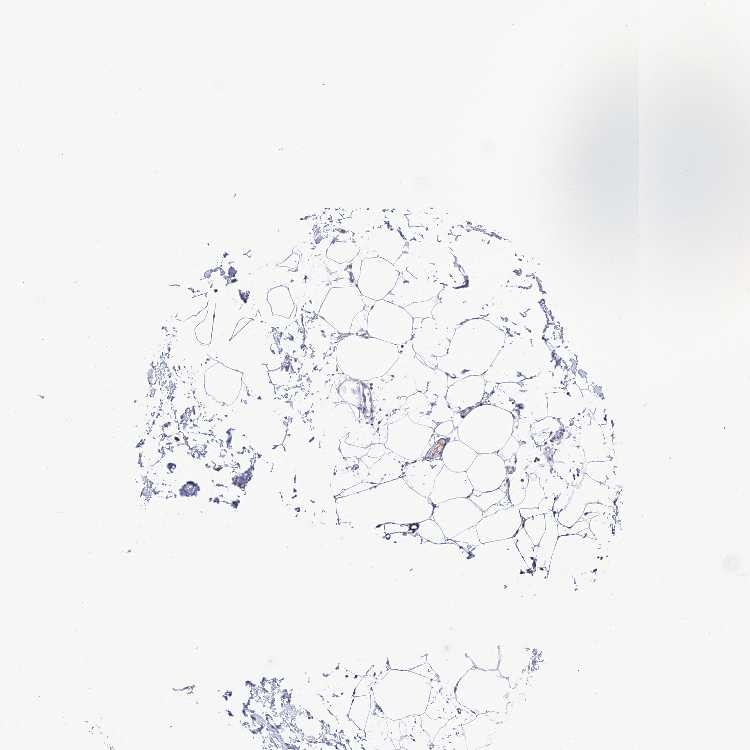

SOFT TISSUE 1 - Antibody stainingi

Antibody staining in the annotated cell types in the current human tissue is reported as not detected, low, medium, or high, based on conventional immunohistochemistry profiling in selected tissues. This score is based on the combination of the staining intensity and fraction of stained cells.

Each image is clickable and will lead to virtual microscopy that enables deeper exploration of all samples and also displays staining intensity scores, fraction scores and subcellular localization as well as patient and tissue information for each sample.

Antibody HPA043789

Fibroblasts Not detected

Peripheral nerve Not detected